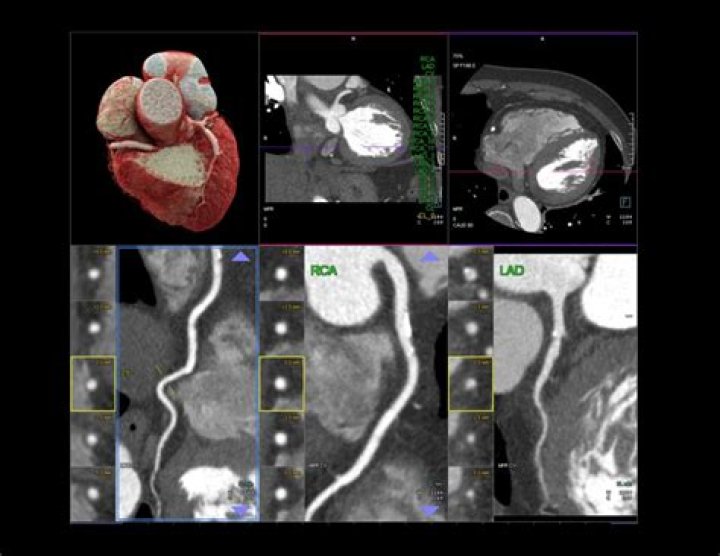

Can a heart CT scan detect blocked arteries?

A CT coronary angiogram can reveal plaque buildup and identify blockages in the arteries, which can lead to a heart attack. Prior to the test, a contrast dye is injected into the arm to make the arteries more visible. The test typically takes 30 minutes to complete.

There are several types of CT scans used in the diagnosis of heart disease, including: Calcium-score screening heart scan. Coronary CT angiography (CTA) Total body CT scan.

A heart CT scan shows detailed images of your arteries, aorta, heart and valves, so that healthcare professionals can measure your heart health without an invasive or lengthy procedure. After your heart CT scan in our low-dose Siemens CT scanner, you will receive your coronary calcium score.

Computed tomography (CT) scan is a type of x-ray that uses a computer to take cross-sectional images of your body. Computed tomography angiography (CTA) combines a CT scan with a special dye or contrast material to produce pictures of blood vessels and tissues in a section of your body.